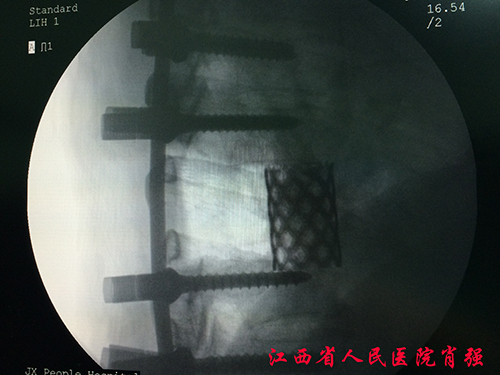

——江西省人民医院成功开展胸椎肿瘤一期后路全脊椎整块切除术 (TES)

47岁的汤先生腰背部疼痛已有11天,来江西省人民医院骨科就诊穿刺活检发现“胸7椎体转移性低分化腺癌”。由于是单发转移,且患者全身情况良好,江西省人民医院骨二科主任医师肖强经过详细的术前评估,周密的术前计划,成功地为患者施行一期后路全脊椎整块切除重建术Total en bloc spondylectomy(TES),完整地切下了肿瘤病椎,术前预估术中出血约3000ml,术前计划输血10单位红悬,1000血浆,而此次术中出血大大少于预期只有1000ml左右,实际输血2单位,血浆400ml,术后患者病情平稳,正在逐步康复。

脊柱肿瘤的手术一直是脊柱外科领域的富有挑战性难题,由于脊柱的特殊解剖,脊髓神经贯穿其中椎管,对发生在脊柱的肿瘤进行根治性全切几乎不可能。以往采用全脊椎分块切除术,俗称“蚕食技术”,将肿瘤游离后,再分块切除。由于切除肿瘤时进入肿瘤组织,所以出血量大,常常4000-5000ml,肿瘤切除往往不彻底、手术区域污染严重,复发率高,而复发的肿瘤几乎无法再次手术。江西省人民医院骨科采用的一期后路全脊椎整块切除术,则是通过单一后方的手术入路,以连接脊椎前后两大块、横截面很细的椎弓根为切割点,将脊椎分成椎弓和椎体两大块完整切除,以椎弓根螺钉固定钛网植骨融合重建,最大限度切除肿瘤降低复发率,对改善脊柱肿瘤的预后具有极其重要的意义。